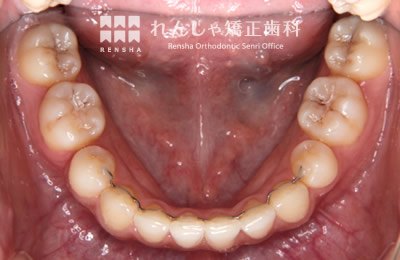

大きながたつきを歯列の拡大で改善しようとすると歯周組織へのダメージや後戻りが問題になります。この様な場合はスペースを確保するために永久歯を抜歯する方法を選択します。歯を抜いてしまうことに不安もあるかと思いますが、抜歯矯正が長い目で見たときにいい結果になることも多いと思います。

治療前

| 主訴 | 叢生 |

|---|---|

| 診断名 | Angle Class I 叢生 |

| 初診時年齢 | 27歳0か月 |

| 装置名 | マルチブラケット装置 |

| 抜歯非抜歯 | 上下顎左右第一小臼歯の抜歯(合計4本) |

| 治療期間 | 2年5か月 |

| 費用の目安 | 約93万円+消費税(検査料金、都度の処置費用等も合わせた総額) |

| リスク副作用 | 歯の移動に伴う軽微な歯根吸収、歯槽骨吸収、歯肉退縮(本症例では軽度の歯肉退縮を認めた)、矯正器具装着中のカリエスリスク増大(本症例ではカリエス発生無し) |